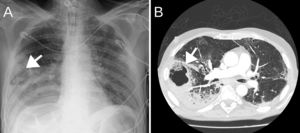

Case 2A 57-year-old man weighing 68kg with a history of active alcoholism, former smoker, laryngectomy in 2016 for supraglottic carcinoma with no evidence of disease, and treated for tuberculosis 15 years earlier. He came to our hospital 6 days after the onset of symptoms consisting of fever peaks and dyspnoea at rest. A chest X-ray performed on admission showed bilateral alveolar infiltrates. SARS-CoV-2 tests were positive, so treatment was started with hydroxychloroquine, lopinavir/ritonavir, amoxicillin-clavulanate, anti-inflammatory therapy with methylprednisolone for 3 days, tocilizumab (2 doses) and tacrolimus. On the ward, he presented delirium, possibly due to alcohol withdrawal. On the sixth day of admission, haemoptysis was observed in the tracheal aspirate, causing tachypnoea and desaturation, so piperacillin-tazobactam was started. Chest X-ray and CT angiography revealed possible right lower lobe (RLL) pulmonary cavitation and PE (Fig. 2).